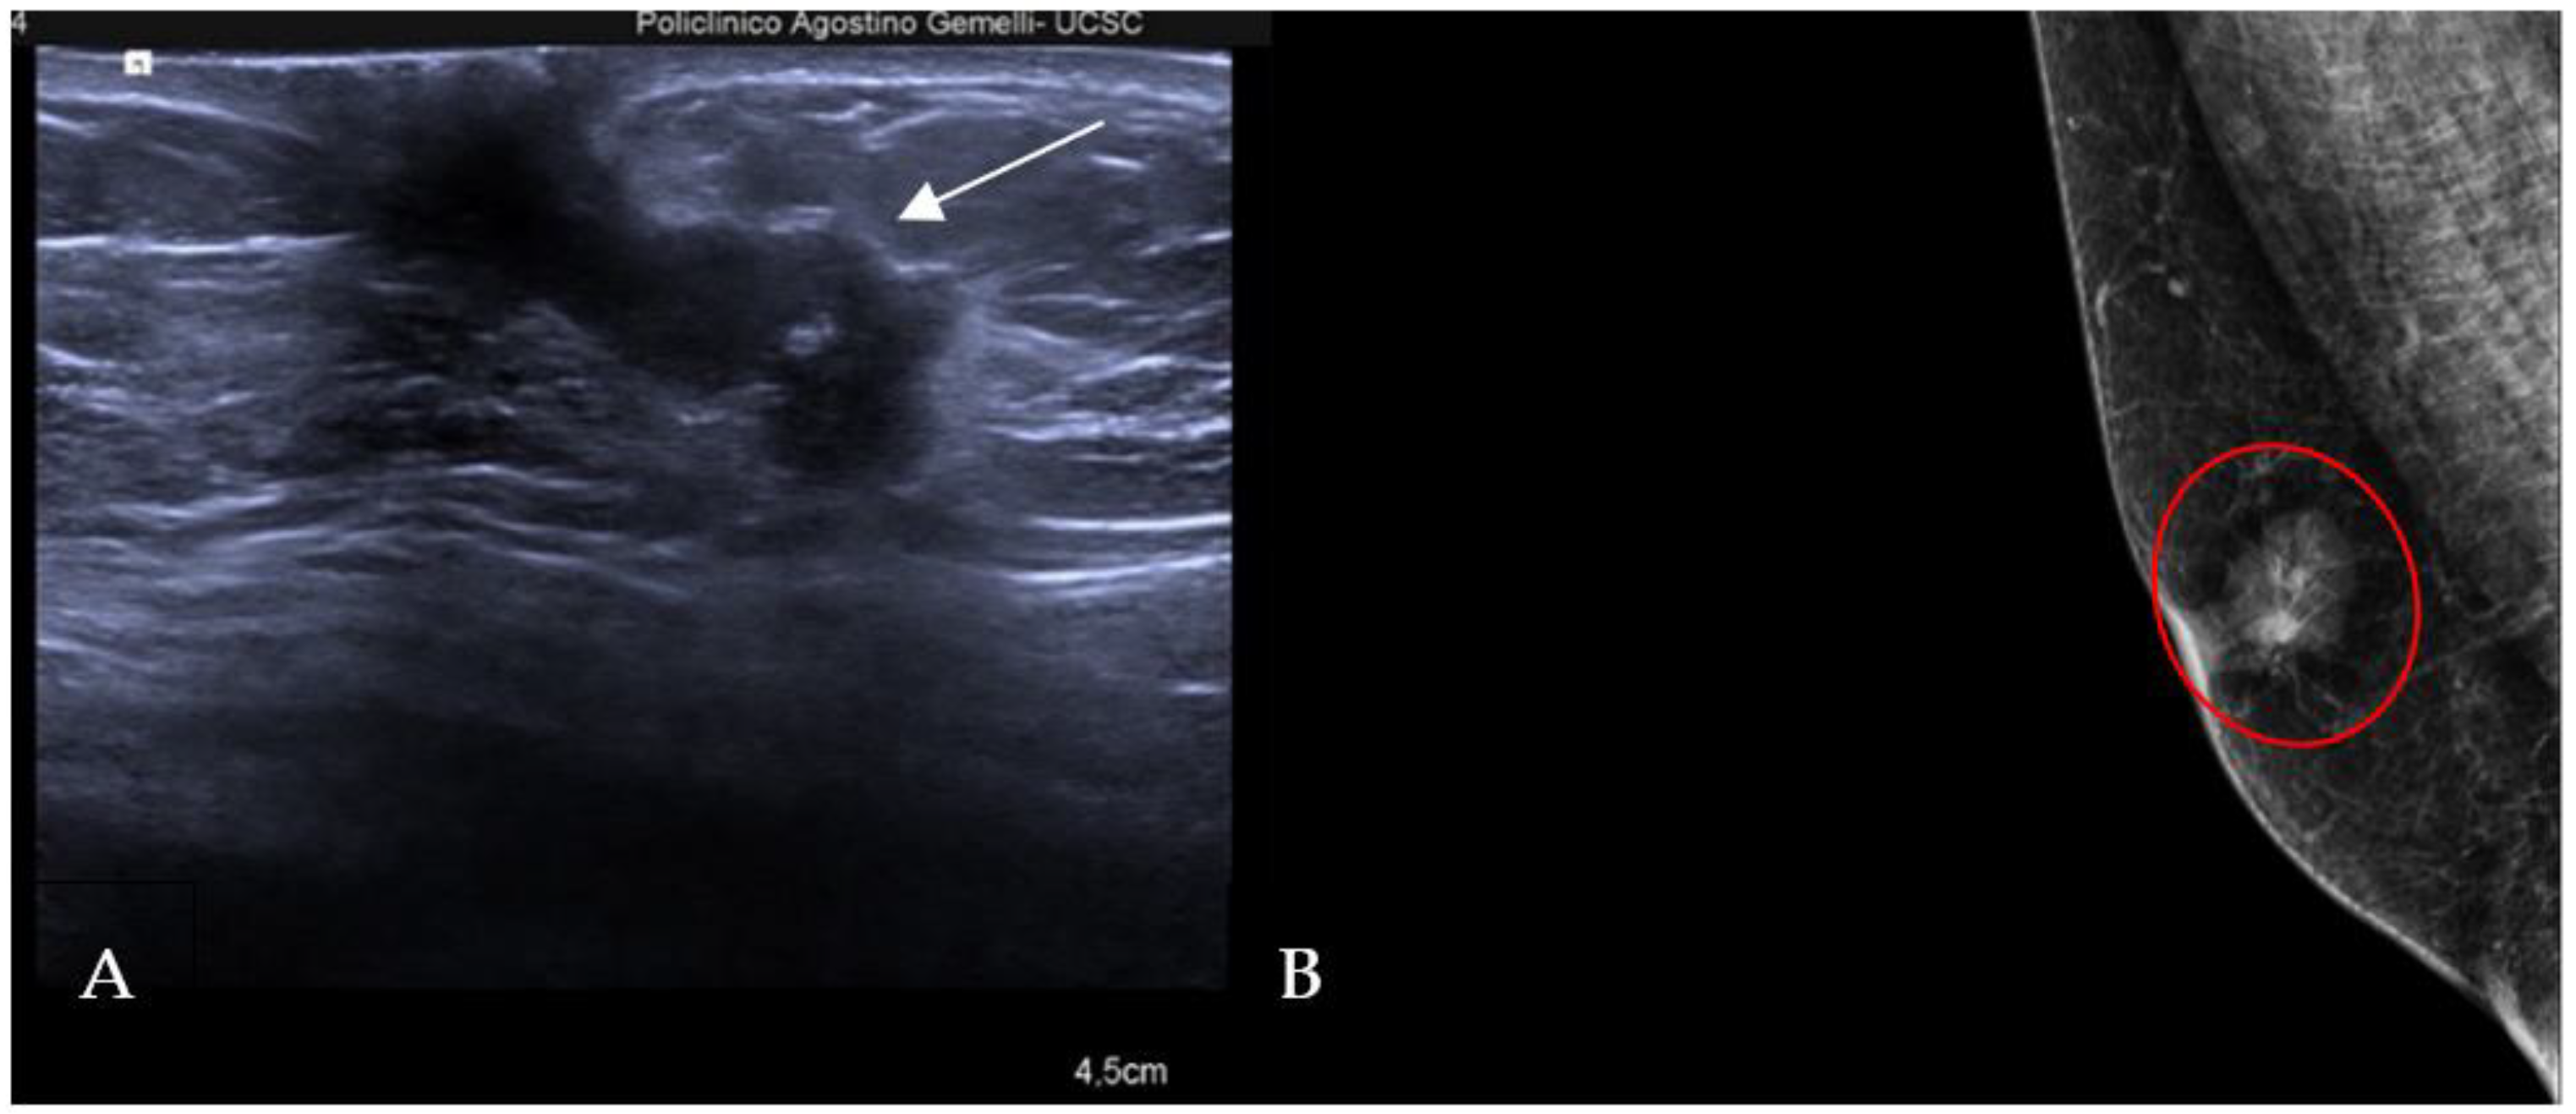

The mammographic assessment reveals three distinct patterns: nodular, dendritic, and diffuse [13]. Nodular gynecomastia is an early and reversible manifestation, appearing as a retro-areolar fan-shaped density with indistinct borders, representing hyperplasia of intraductal epithelium and stromal edema. Dendritic gynecomastia indicates the fibrotic phase, characterized by dilated ducts and hyalinized stromal fibrosis. Mammographic features include a flame-shaped density with linear finger-like projections into the subareolar fatty tissue. Diffuse gynecomastia results from chronic estrogen exposure and can exhibit features of both nodular and dendritic forms or resemble the architecture of the female breast [5]. Pseudo-gynecomastia, primarily observed in overweight or obese individuals, results from excessive fatty tissue stimulation without fibro-glandular components and is a key differential diagnosis to consider (Figure 2).

Figure 2.

Right medio-lateral-oblique digital mammography of different types of male breast. (A) Pseudo-gynecomastia: the breast is almost entirely fatty. (B) Nodular gynecomastia: in the retro-areolar region, there is a nodular density that blends into the surrounding subcutaneous fat, resulting in indistinct border. (C) Dendritic gynecomastia: there are fibrous extensions of dendritic gynecomastia (flame shaped) in the breast. (D) Diffuse gynecomastia: heterogeneously dense breasts consisting of both nodular and dendritic components that closely resemble female breasts in a transgender patient receiving high-dose estrogen therapy.